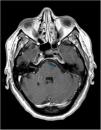

Vasculitis primaria del sistema nervioso central. Una enfermedad rara con alta mortalidad

Primary central nervous system vasculitis. A rare disease with high mortality